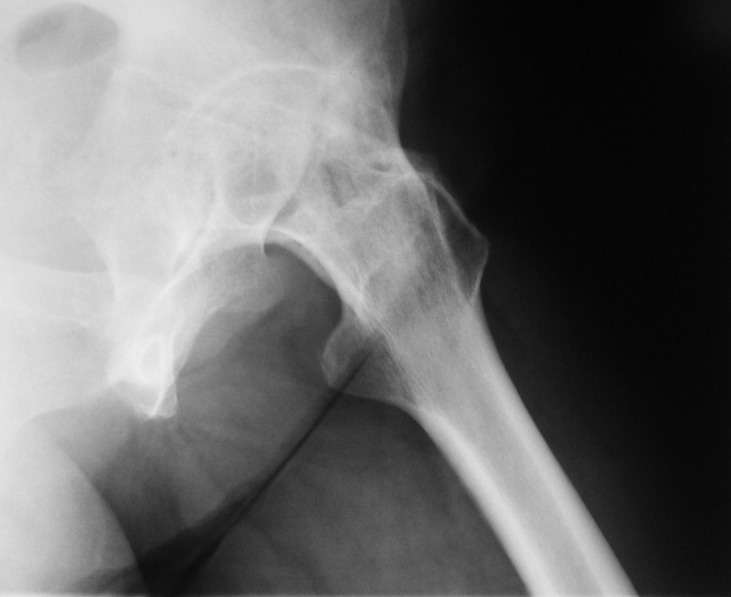

При обследовании выявлен анкилоз тазобедренного сустава в приведении. Видимо, в период пребывания в тяжелом состоянии появились гетеротопические оссификаты. За исключением того, что осталась одна почка, сейчас других медицинских проблем нет.

Пациентку в первую очередь беспокоят боли в спине, на отсутствие движений в суставе она вроде и не жалуется. Вопрос насчет тактики. Корсет и анальгетики вряд ли решение. Первый вариант - удаление оссификатов и эндпротезирование, второй - корригирующая остеотомия в проксимальном отделе с устранением порочного положения.

Боли в спине обусловлены порочным положением бедра. Эндопротезирование более интересно, т.к. дает еще и движения в суставе (кроме устранения порочного положения). Оссификаты не страшные, а учитывая срок (3 года) - уже созревшие. Я зарекся делать ЭТС при больших оссификатах - очень частый рецидив даже на фоне индометацина и луч.терапии.

Я думаю, что эндопротезирование - более предпочтительный вариант у пациентки 53 лет. К тому же суставная щель прослеживается и, вероятнее, большой сложности с установкой вертлужного компонента не будет. Высока вероятность необходимости аддуктотомии.

В любом случае замена сустава после оссификации дело не благодарное - безболезненная контрактура станет болезненной контрактурой.